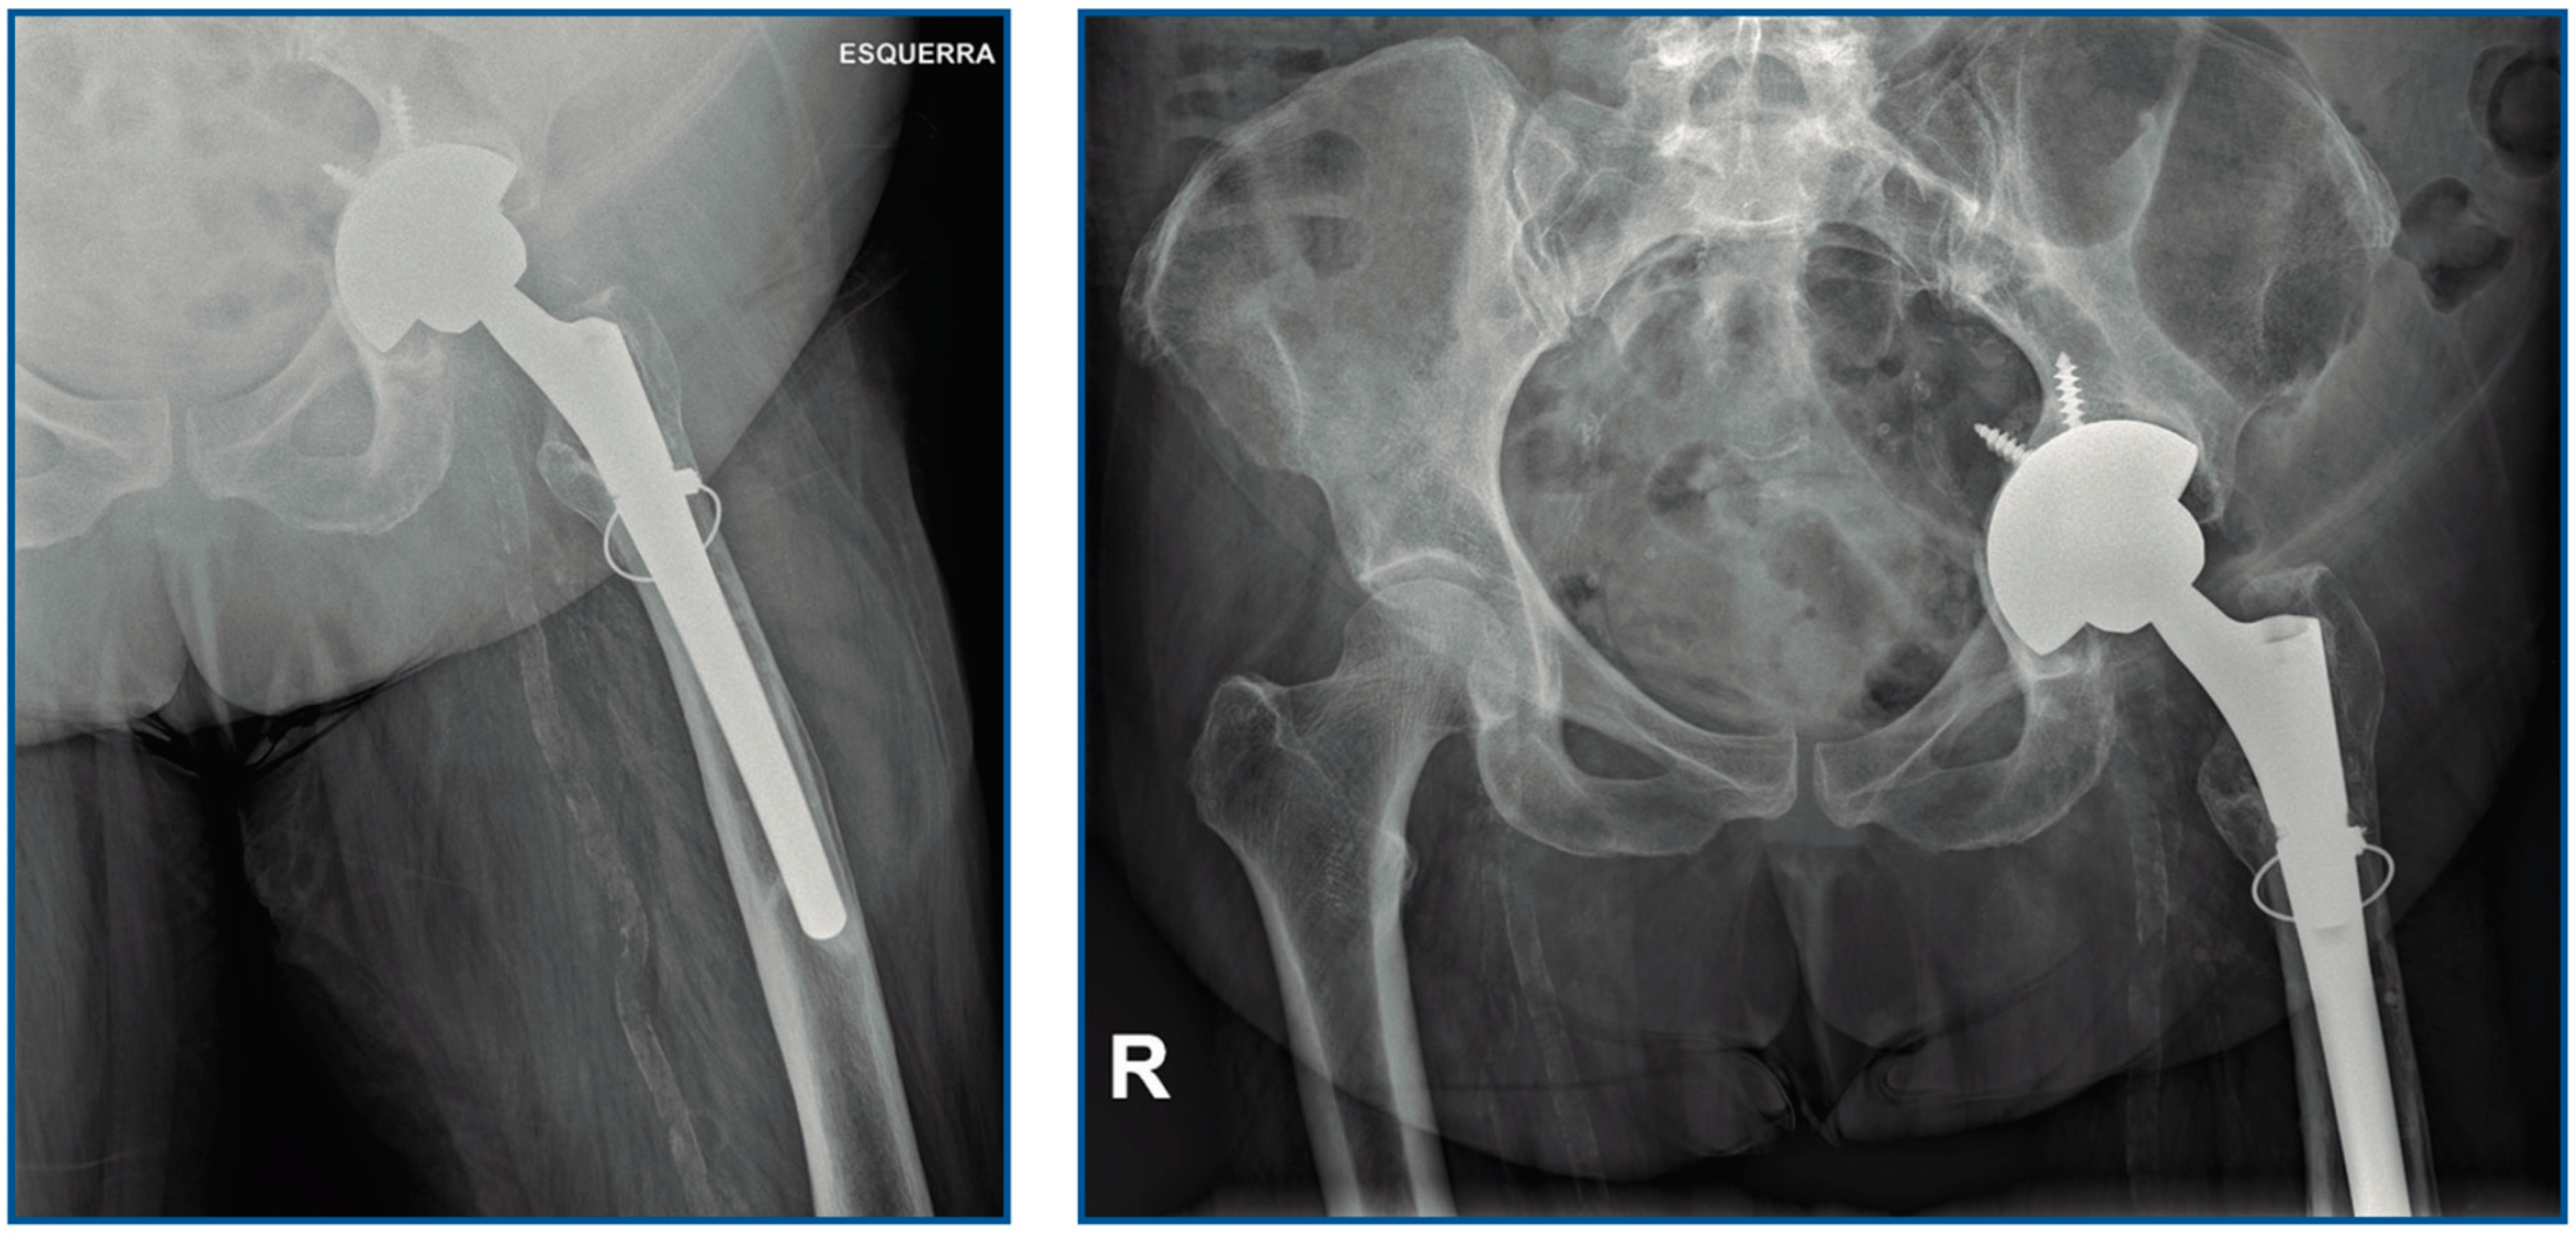

| Present case, 2021 | Female, 60 | Total hip arthroplasty | Cirrhosis | DAIR. Second DAIR after 10 d | Daptomycin, cloxacillin and ceftazidime 4 d. Cefotaxime and metronidazole 2 w Amoxicillin 4 w |